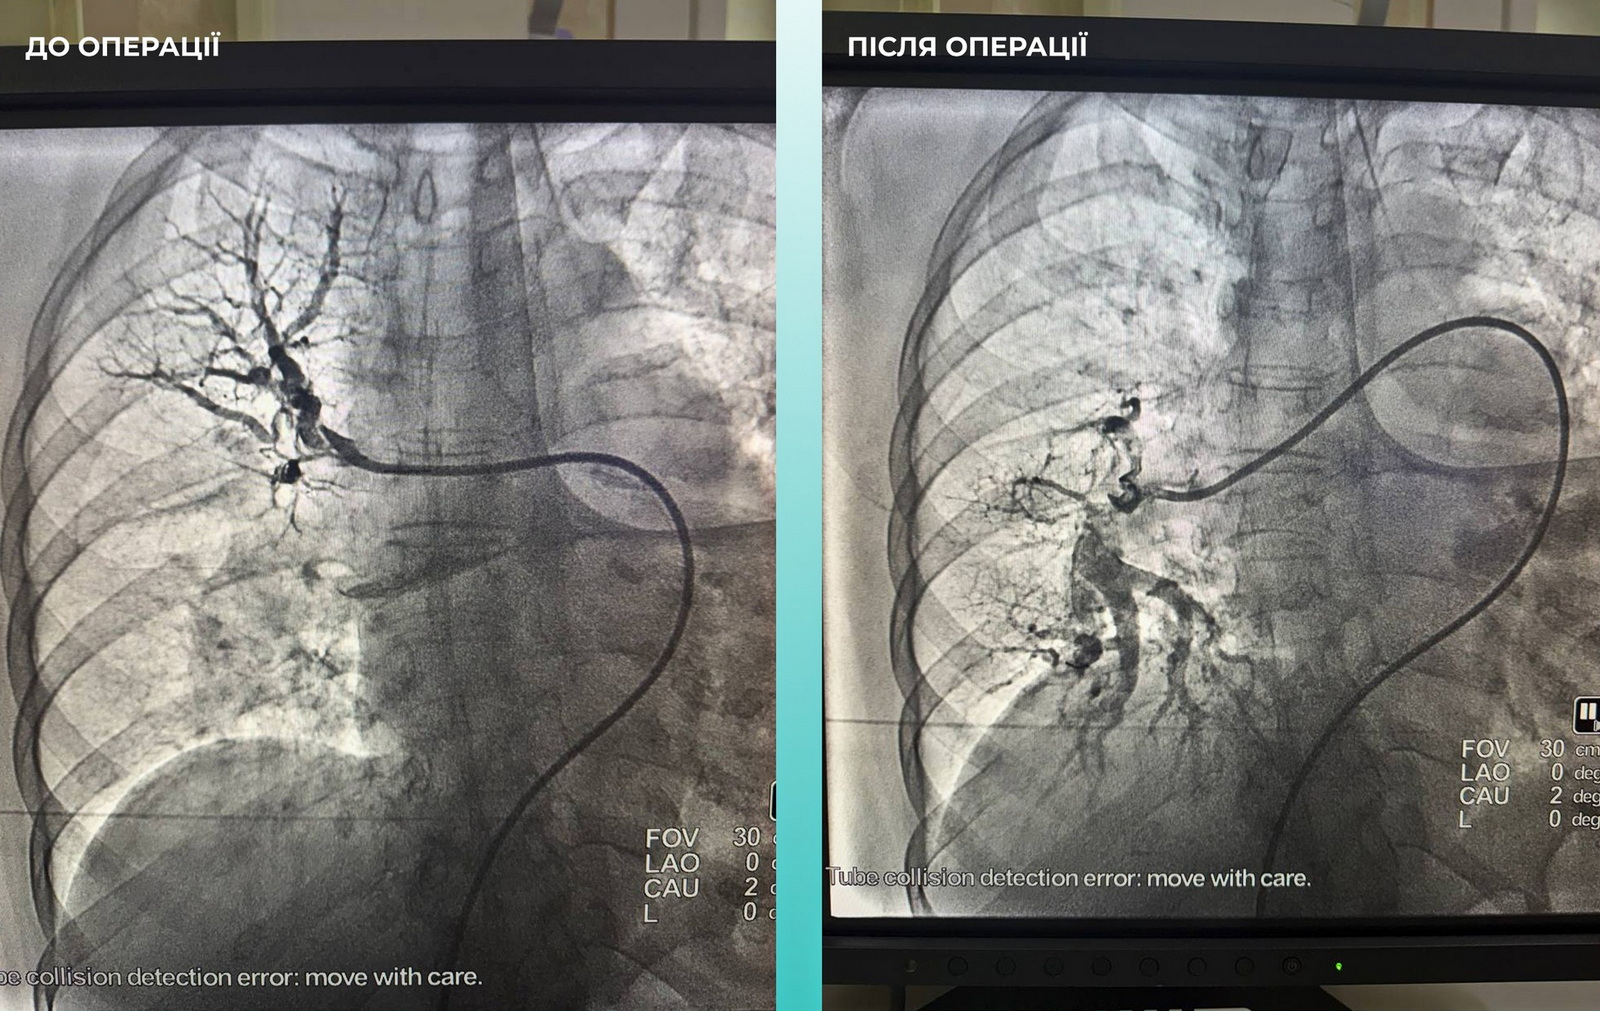

Одеситка потрапила до лікарні з важким гострим мозковим інсультом. Під час обстеження на комп’ютерному томографі лікарі виявили закриття середньої мозкової артерії. Також медики звернули увагу, що жінці важко дихати, тож додатково обстежили легені. Діагноз ускладнився ще й тромбоемболією легеневої артерії.

Мультидисциплінарна команда лікарів ухвалила життєво необхідне рішення – провести одночасну тромбектомію з мозкової та легеневої артерій.

Операція пройшла успішно, наразі стан пацієнтки значно покращився.